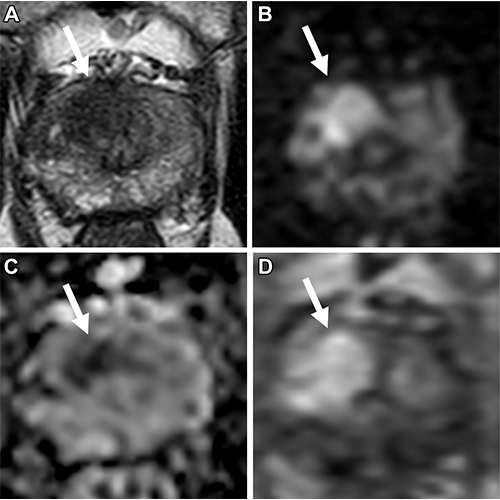

Multiparametric MRI in a 77-year-old man with an elevated prostate-specific antigen level of 10.7 ng/mL and a Prostate Imaging Reporting and Data System category 5 lesion located in the right apical-base anterior transition zone. (A) Axial T2-weighted image shows hypointense appearance of the lesion (arrow). (B) High–b value (b = 1500 sec/mm2) diffusion-weighted image shows high signal intensity of the lesion (arrow). (C) Apparent diffusion coefficient map generated using b values of 0, 300, and 600 sec/mm2 shows low signal intensity of the lesion (arrow). (D) Dynamic contrast-enhanced image shows early enhancement of the lesion (arrow). MRI/US fusion–guided biopsy revealed clinically significant prostate cancer with an International Society of Urological Pathology grade of 3. https://doi.org/10.1148/radiol.221309 ©RSNA 2023